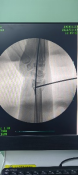

術中透視

患者男性,54歲,外傷致右側脛腓骨開放性骨折8小時,局部可見右側脛骨骨折近端露出···